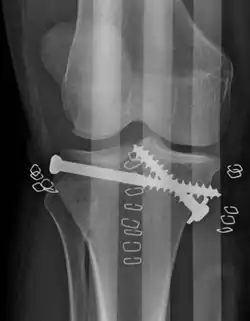

Una fractura de meseta tibial vista con rayos-X

Tratamiento

El tratamiento está enfocado en lograr una articulación estable, alineada, móvil e indolora y en minimizar el riesgo de osteoartritis post-traumática. Para lograr esto, los médicos consideran planes operativos y no-operativos basados en el criterio formado por las características del paciente, la gravedad de la lesión, el riesgo de complicaciones, la depresión y desplazamiento de la fractura, el grado de lesión a los ligamentos y meniscos y el grado de riesgo vascular y neurológico. Para los primeros tratamientos, se debe realizar tracción de manera temprana en la sala. Puede ser tracción cutánea o esquelética. Depende del peso del paciente y de la estabilidad de la articulación. Se introducen tornillos de Schantz sobre el calcáneo y deben ser introducidos del lado medial al lateral. Una vez que la condición sea estable, el plan definitivo deberá reforzar la galvanoplastia y el tornillo de compresión de fijación.